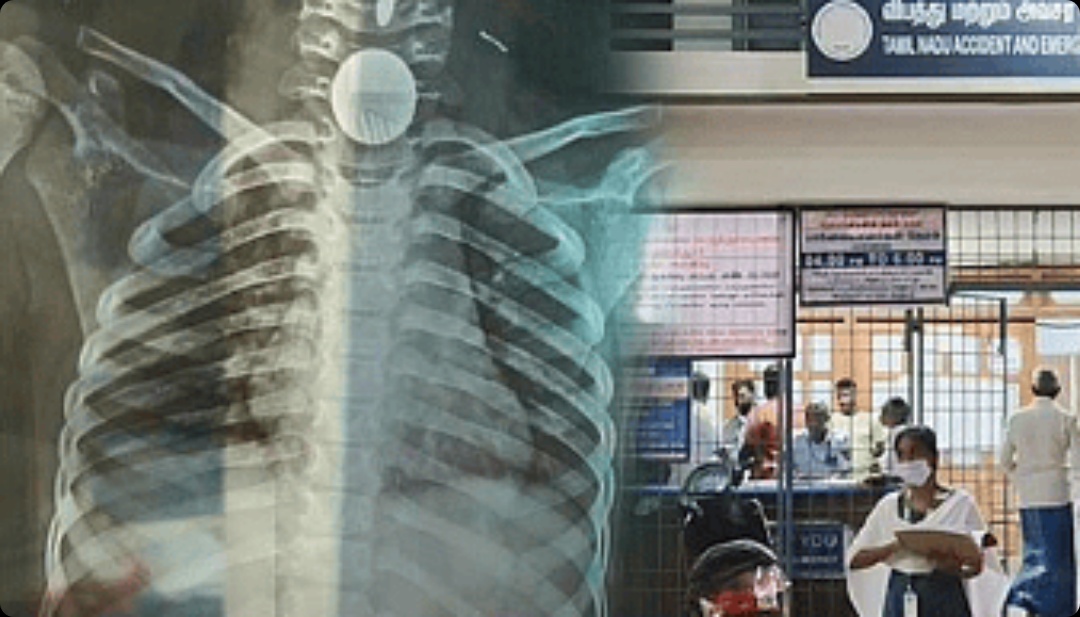

ஐந்து ரூபாய் நாணயத்தை விளங்கிய சிறுமி: அரசு மருத்துவமனை காப்பாற்றி சாதனை

திருப்பத்தூர் : திருப்பத்தூர் மாவட்டத்தில் ஐந்து ரூபாய் நாணயத்தை விழுங்கிய சிறுமியை காப்பாற்ற முடியாது என தனியார் மருத்துவமனை கைவிட்ட நிலையில் உயிரை காப்பாற்றி அரசு மருத்துவமனை சாதனை படைத்துள்ளது.

இந்நிலையில் சிறுமி வீட்டின் வெளியே விளையாடிக் கொண்டு இருந்துள்ளார். அப்போது அவரது பாட்டி சிறுமியிடம் 5 ரூபாய் நாணயம் ஒன்றை கொடுத்துள்ளார். இதை வாங்கிய சிறுமி, தவறுதலாக விழுங்கியுள்ளார்.

இதில் சிறுமிக்கு மூச்சு திணறல் ஏற்பட்டுள்ளது. உடனே இதுபற்றி அறிந்த பெற்றோர் சிறுமியை அருகே உள்ள தனியார் மருத்துவமனைக்கு அழைத்துச் சென்றுள்ளனர். அங்கு சிறுமியை காப்பாற்ற முடியாது என மருத்துவர்கள் கூறியுள்ளனர்.

பிறகு, சிறுமியின் பெற்றோர்கள் சற்றும் தாமதிக்காமல் திருப்பத்தூர் அரசு மருத்துவமனைக்கு கொண்டு வந்தனர். அங்கு பரிசோதித்த மருத்துவர்கள் உடனே சிறுமியின் உடல் நிலை குறித்து காது மூக்கு தொண்டை நிபுணரான தீபானந்தனுக்கு தகவல் கொடுத்துள்ளனர்.

இந்த மருத்துவர் விடுமுறையில் இருந்தபோதும், 7 வயது சிறுமியின் நலன் கருதி விரைந்து மருத்துவமனைக்கு வந்து உரிய சிகிச்சை கொடுத்த உயிரை காப்பாற்றியுள்ளார். இதையடுத்து மருத்துவக்குழுவிற்கு சிறுமியின் பெற்றோர் கண்ணீர் மல்க நன்றி தெரிவித்தனர்.

”அரசு மருத்துவமனையில் வேலை செய்கிறோம். அவசரம் என்ற சூழ்நிலையில் ஓடி வருவதுதானே மனிதாபிமானம்” என மருத்துவர் தீபானந்தன் நெகிழ்ச்சியுடன் தெரிவித்துள்ளார்.